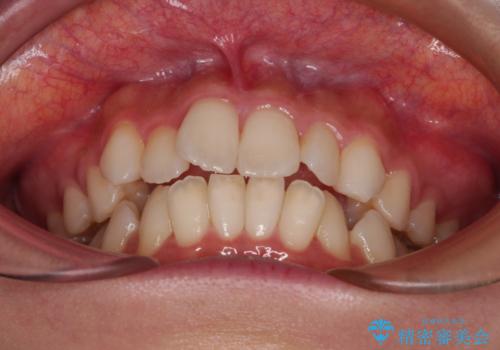

- 口元の突出感と口の閉じにくさを気にして来院された患者様です。

上下左右第一小臼歯4本を抜歯し、ワイヤー装置にて口元を引っ込めるよう矯正治療を行うこととしました。

口元の突出感が改善されてことで、下唇に引っかかっていた上顎前歯も気にならなくなりました。